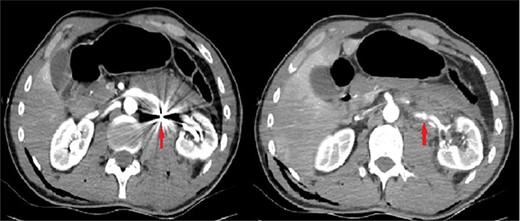

The patient was re-evaluated with CTA 3 weeks after discharge. Endovascular intervention was planned after observing that the left RAP was enlarged to 6 mm (Fig. 2). A renal angiogram was performed. After selectively catheterizing the left renal artery, a 6 × 3 mm filling extending inferiorly in the middle part of the left renal artery compatible with RAP was observed (Fig. 3). Following catheterization of the left renal artery with a long sheath, the lesion segment was passed with guide wire-catheter manipulations. Subsequently, a 6 × 22 mm covered stent (Advanta V12 Balloon Expandable Covered Stent, AMC, USA) was placed to include the RAP neck, and full expansion of the balloon and stent was achieved (Fig. 3). The control images revealed that the RAP was excluded from circulation, and the stent was patent. No embolism or bleeding was observed in the distal renal artery branches.

The filling image of the left renal pseudoaneurysm and the inserted covered stent.